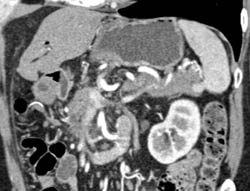

Chronic Pancreatitis With Encased PV/SMV